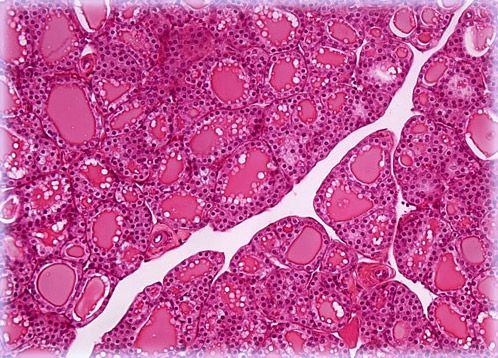

The thyroid is an endocrine gland situated in the throat that produces hormones that are involved in various functions within the body. Comprised of two oblong lobes linked by a narrow piece of tissue called the isthmus, the thyroid contains millions of small sac-like follicles that store the important substances.